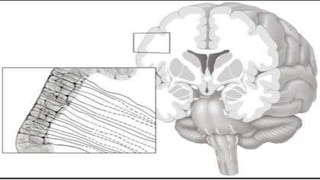

• Tractography is a 3D modeling technique used to visually represent nerve

tracts using data collected by diffusion MRI. It uses special techniques of

magnetic resonance imaging and computer-based diffusion MRI.